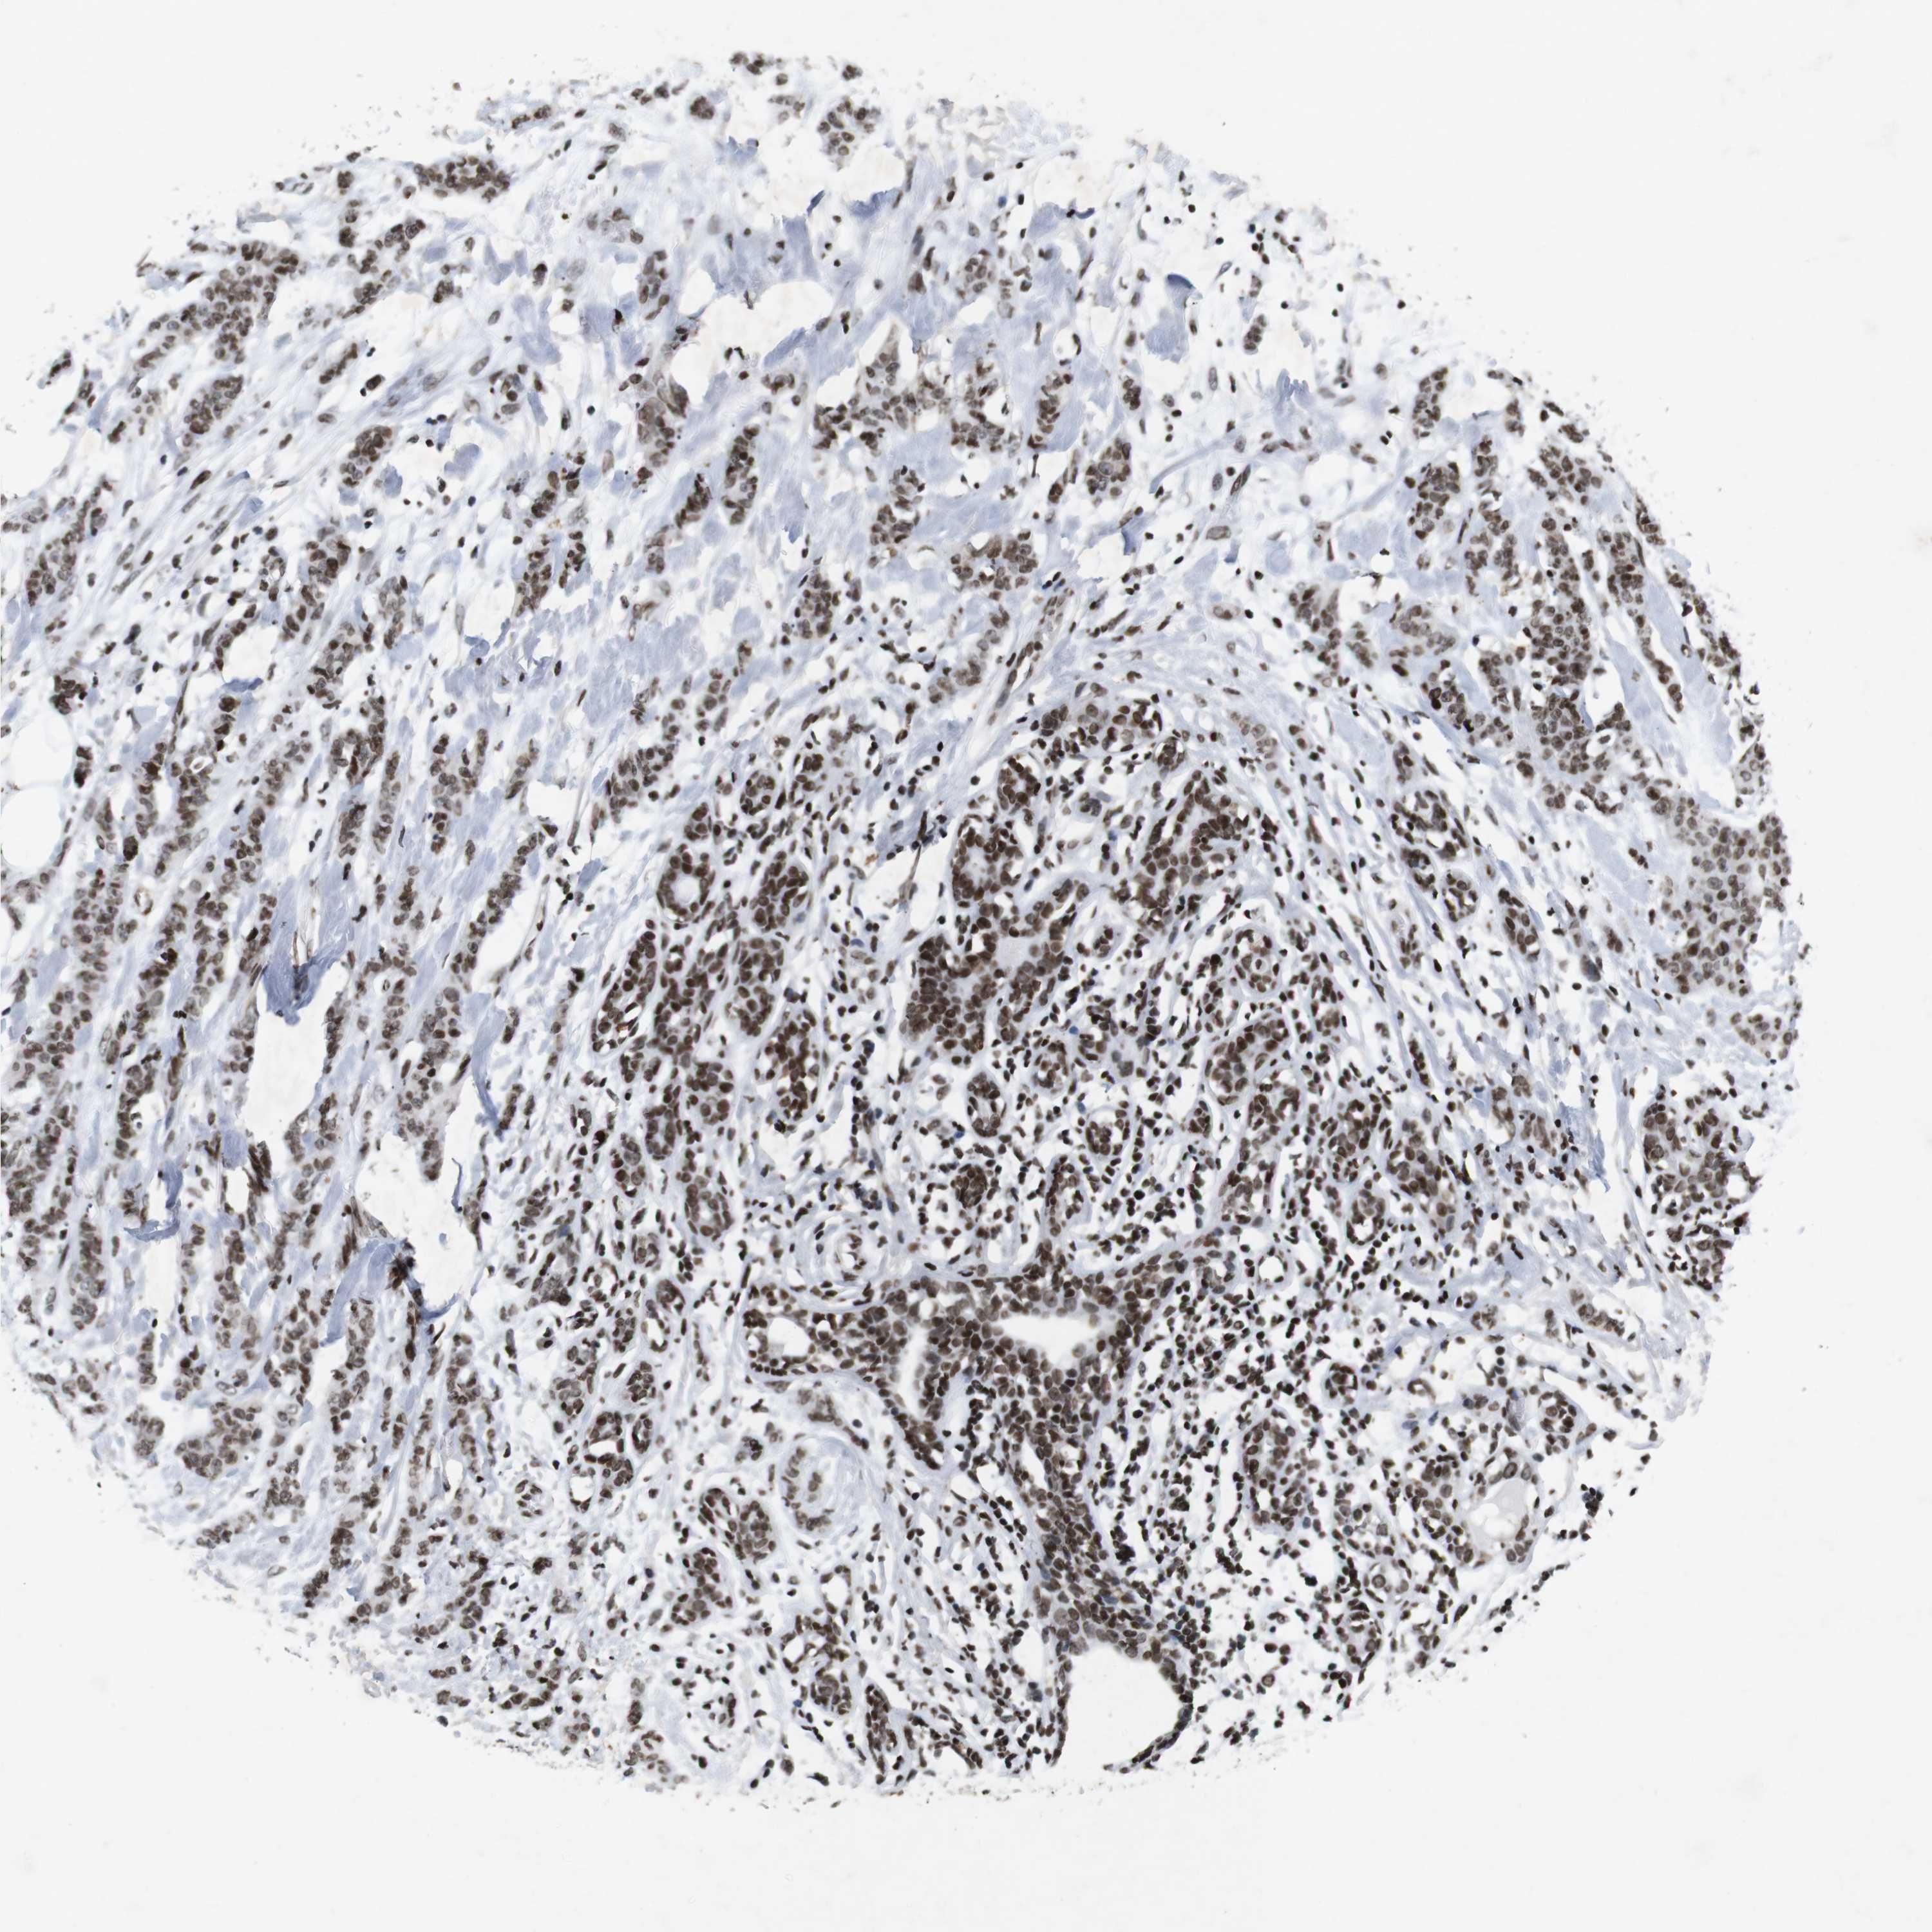

CANCER BREAST CANCER Show tissue menu

BRCA TCGA BRCA VALIDATION PROTEIN EXPRESSION